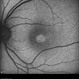

- Chloroquine maculopathy

- chloroquine maculopathy, drug toxicity

- Fundus of the left eye of a 56 year-old female with history of rheumatoid arthritis treated with chloroquine.